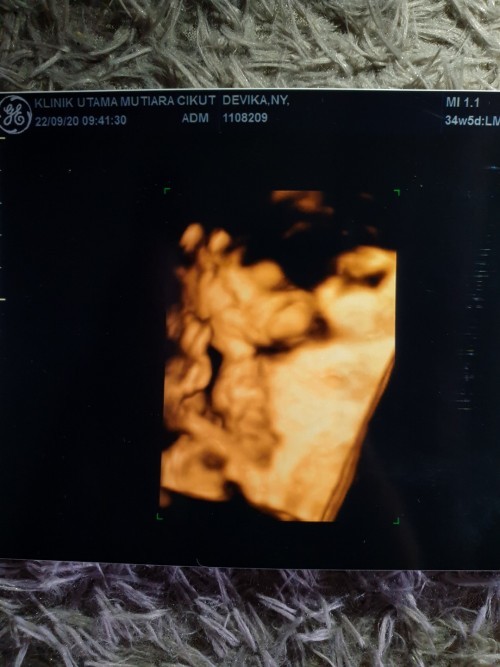

Ini bunda foto usg baby aku

hpl 27 Nov pas usg 8 Bulan